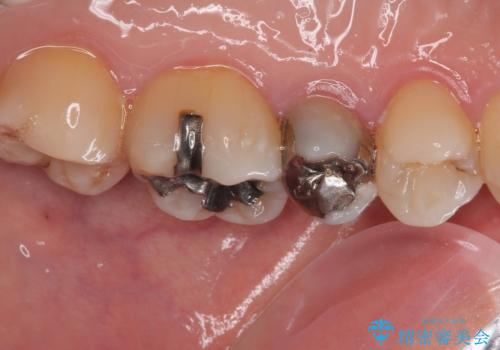

- むし歯と銀歯を気にして来院された患者様です。

銀歯の歯は既に根管治療がされており、根尖部に病変が認められないため、根管治療を行うことなくオールセラミッククラウンにて補綴治療を行うこととしました。

むし歯の症状のある歯は、ややしみることがある程度でしたが、レントゲン写真では非常にむし歯が大きく、神経組織に迫っている状態でした。

術前診査では神経を全て取る可能性は低いと予想されましたが、一部切除する可能性があることを伝えた上で治療を行うこととしました。